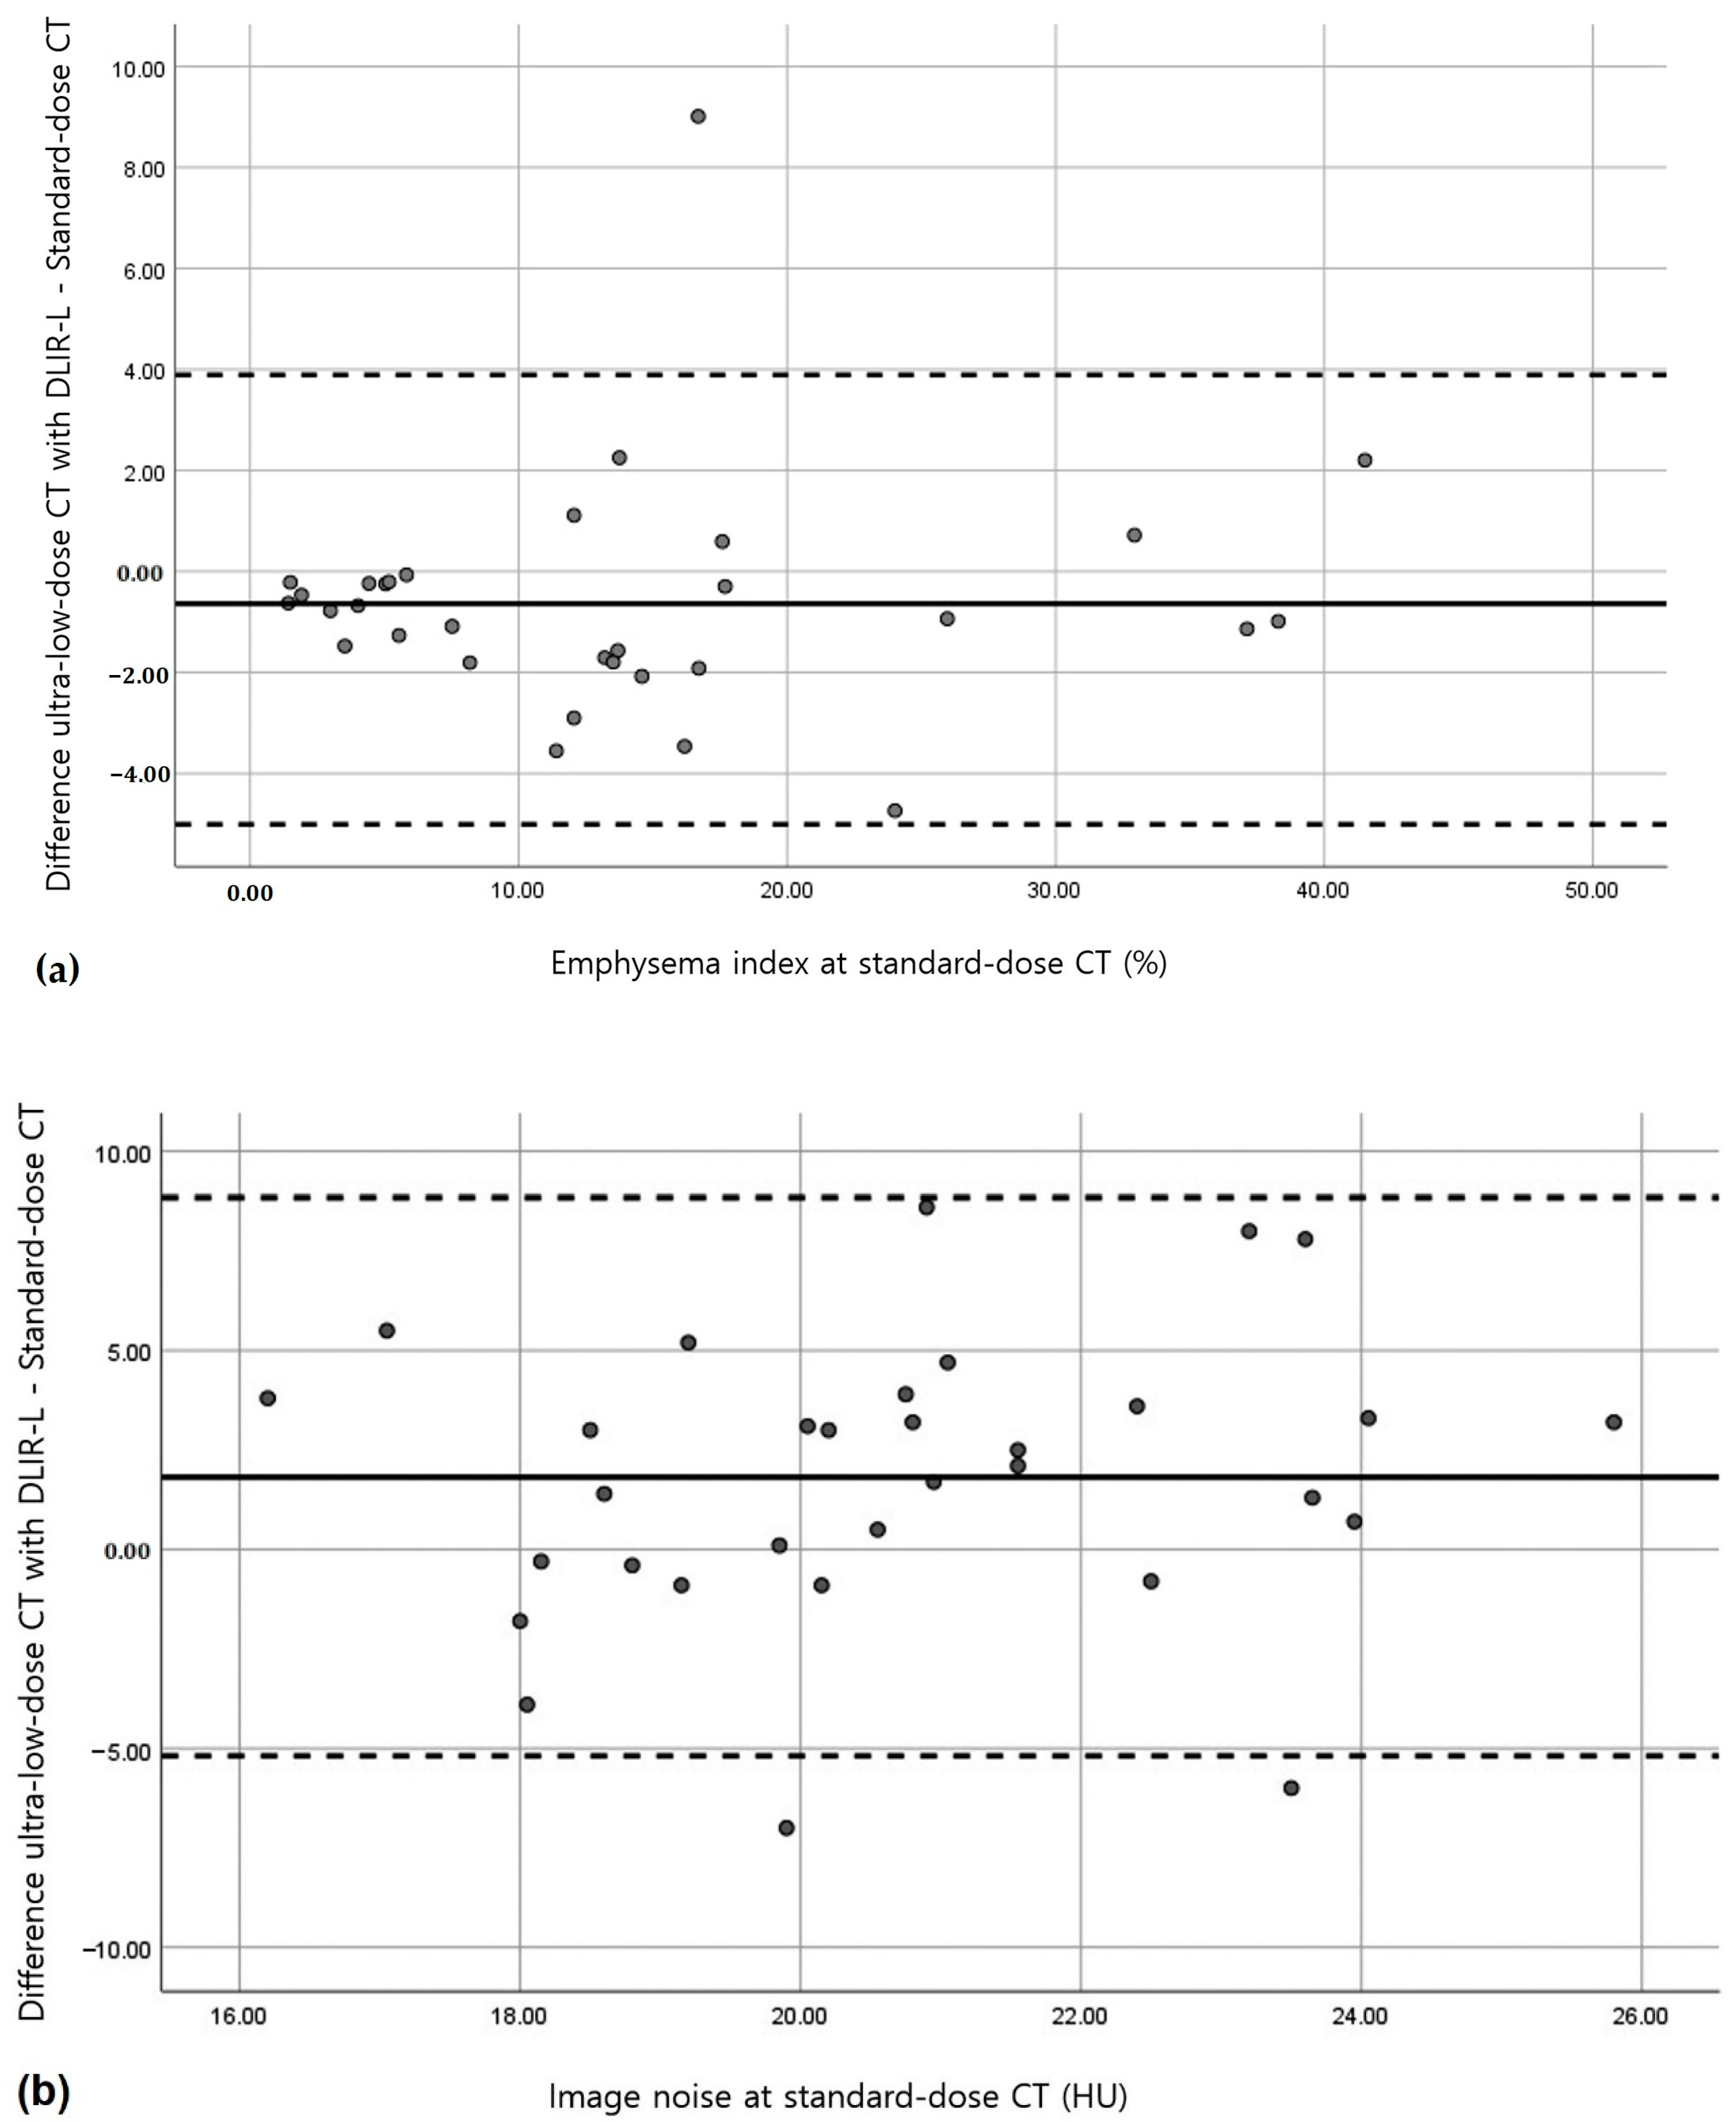

3.2. Quantitative Measurements of Standard-Dose and Ultra-Low-Dose CT

4. Discussion